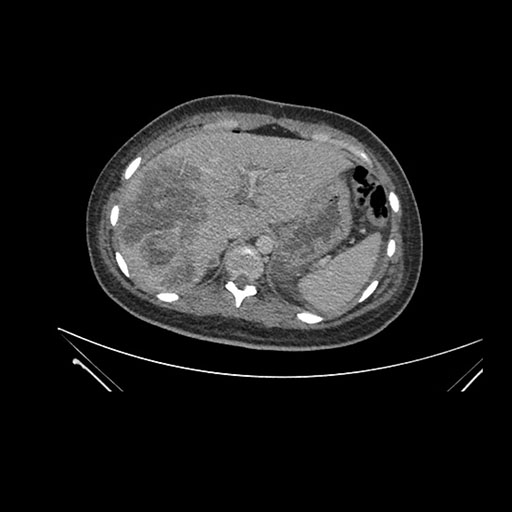

Imaging Analysis

Look through the patient's CT scan to identify any areas of concern for the necessary procedure.

Coronal Arterial

Based on initial findings, which issue(s) would you be most concerned about?